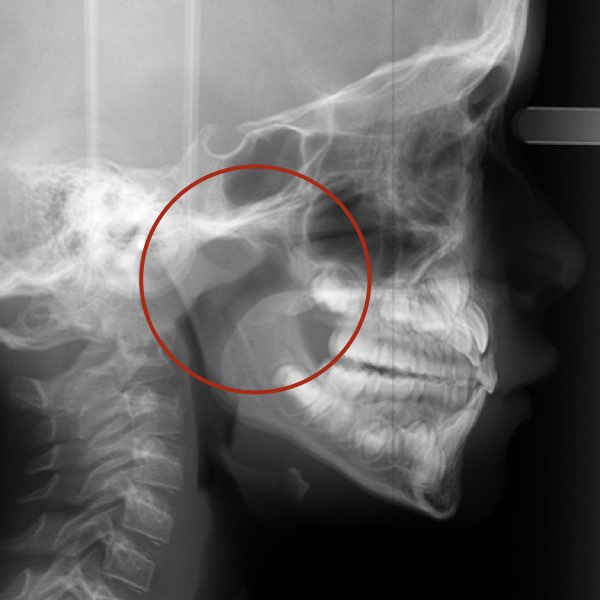

Na verdade, o diagnóstico será baseado em um primeiro momento na presença ou ausência da obstrução anatômica da via aérea em si. Nas imagens abaixo é possível ver através da telerradiografia em norma lateral a presença ou não da obstrução da via aérea superior. Sendo que diante da obstrução anatômica nossa conduta como profissionais deve ser o encaminhamento para médico do sono ou otorrino pediátrico, independente da necessidade de expansão maxilar ou protração.